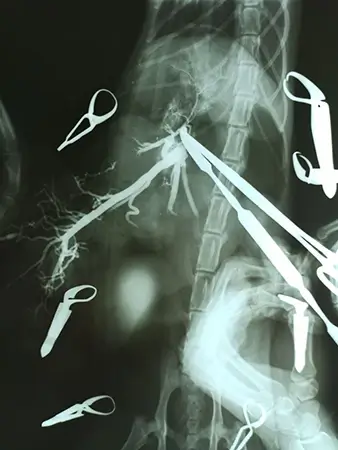

2. Контрастна рентгенографія (портографія) – найбільш точний та простий метод. Полягає у введенні в судинне русло контрастної речовини та рентгенологічне дослідження анатомії судин. Допомагає виявити більшість аномалій.

ПСШ- частіше це одна велика судина, що з’єднує систему воротної вени з центральним кровотоком (каудальна порожниста вена чи непарна вена), минаючи печінку.

ПСШ - частіше це одна велика судина, що з’єднує систему воротної вени з центральним кровотоком (каудальна порожниста вена чи непарна вена), минаючи печінку.